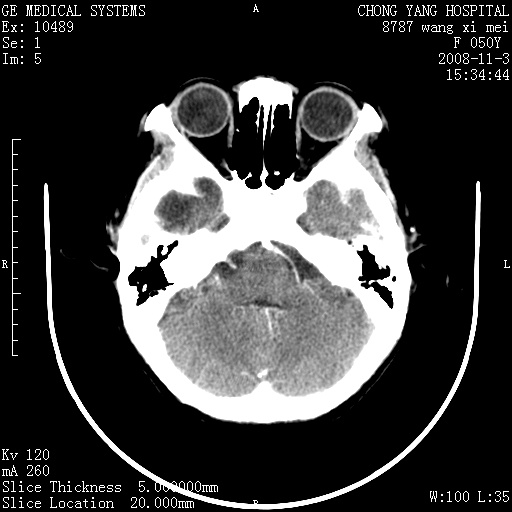

标题: CT16469:女,50岁,胶质瘤术后6年,今平扫加增强,请大家帮 [打印本页]

标题: CT16469:女,50岁,胶质瘤术后6年,今平扫加增强,请大家帮

右侧颞顶部可见低密度实变影,内见不规则钙化灶,边界不清,占位效应明显,侧脑室后角受压移位,符合胶质瘤术后复发改变。

右颞骨局限性缺如,局部脑组织无外隆。右颞叶可见片状脑脊液样低密度影,边缘较清,右侧侧脑室三角区可见一块状等密度影,且伴有强化,余未见明显异常改变。

考虑:右大脑术后改变伴肿瘤复发。

手术后局部片状低密度改变(软化灶),其后方颞叶似等密度病灶,界限不清,内见钙化,有轻度占位效应,但增强后强化之血管走行如常。应不考虑:复发!